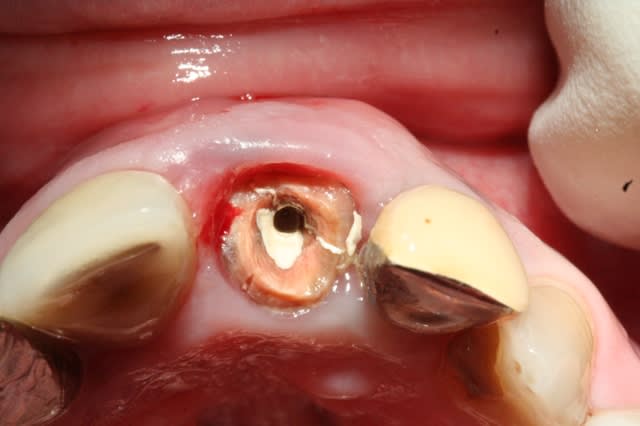

voici la radio

Radio 21 fractur e kbb2or - Eugenol